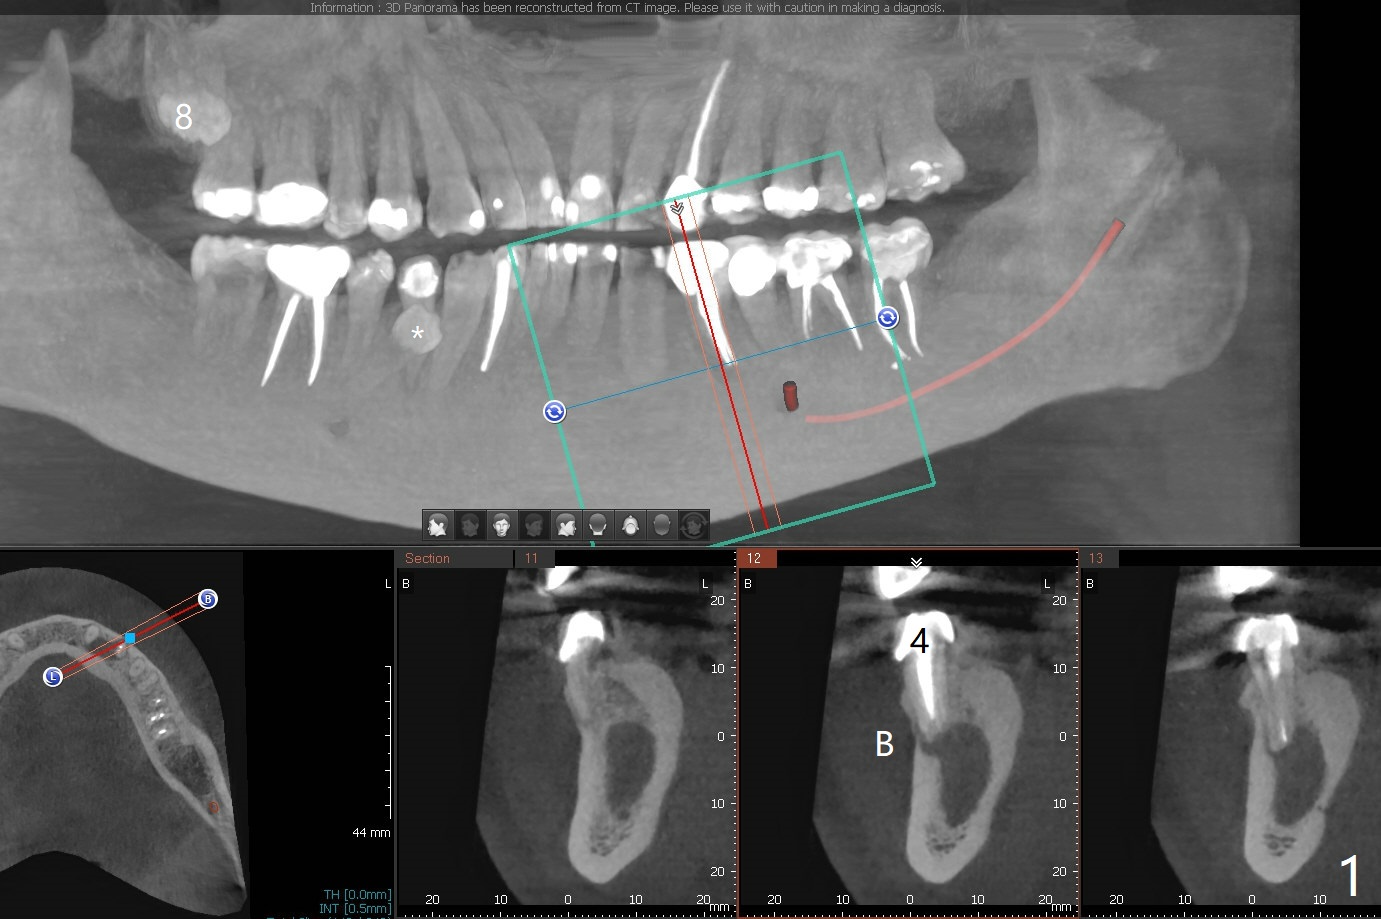

38岁男,十几岁左下4在台湾做根管治疗,八年前外州美国牙医重做根管治疗,他成为我们病人约五年,根尖阴影一直存在,由于无症状,没有引起重视。不过近半年主诉左下唇偶尔麻木,全景片似乎显示左下4根尖阴影相当大,今天CT检查证实这一点(图一),仿佛是根尖囊肿;右下前磨牙区多生牙(*),右上8颊侧也有一个多生牙(图二:8')。虽然病人恐惧手术,但是他不愿意去看专家。尽管囊肿大,累及邻牙,尤其是左下三(图三(可能死髓,Endo Ice; Electric Pulpal Tester;根管治疗)),但是首先做根尖半月形切口,做比较大的根尖切除术,试图刮治囊肿。如果手术当时刮治不全,拔除患牙,增加视野,彻底刮治,填入大量粘性骨块(图四:红圆圈),覆盖PRF膜,缝合,牙周敷料。由于工作需要,病人说他不能没有牙,如果可能,做即刻植牙(图四:绿色),即刻无咬合修复。准备Collagen or Osteogen Plugs,压迫止血。